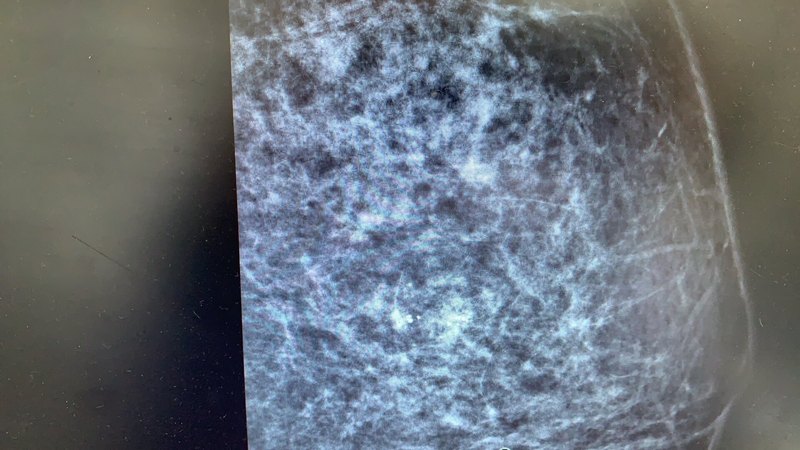

乳腺葉狀腫瘤是一種相對罕見但值得關注的乳腺疾病,它占所有乳腺腫瘤的不到1%。這種特殊類型的腫瘤因其在顯微鏡下呈現(xiàn)的"葉狀"結構而得名,臨床表現(xiàn)和治療方式與常見的乳腺癌有所不同。本文將帶您全面了解乳腺葉狀腫瘤的基本特征、診斷方法和治療選擇,幫助您認識這一特殊疾病。什么是乳腺葉狀腫瘤?乳腺葉狀腫瘤是一種由乳腺間質(支持組織)和上皮(腺體)成分共同構成的腫瘤,其名稱來源于顯微鏡下觀察到的特征性"葉狀"或"分葉狀"生長模式。這類腫瘤最早于1838年被描述,直到1982年世界衛(wèi)生組織(WHO)才正式將其命名為"葉狀腫瘤"。從生物學行為來看,乳腺葉狀腫瘤可分為三大類:良性葉狀腫瘤:約占所有葉狀腫瘤的60-70%,生長相對緩慢,轉移風險低交界性葉狀腫瘤:約占15-20%,具有潛在惡性傾向惡性葉狀腫瘤:約占10-20%,具有明顯的惡性特征,可能發(fā)生遠處轉移值得注意的是,即使是良性葉狀腫瘤,也有局部復發(fā)的可能性,因此所有葉狀腫瘤都需要醫(yī)療關注和適當處理。乳腺葉狀腫瘤的臨床表現(xiàn)乳腺葉狀腫瘤通常表現(xiàn)為無痛性、可觸及的乳房腫塊,患者自己或醫(yī)生在體檢時發(fā)現(xiàn)。這些腫塊通常具有以下特點:生長速度:可能長時間保持穩(wěn)定,也可能在短期內迅速增大(特別是惡性葉狀腫瘤)大?。翰町惡艽螅瑥?-2厘米到巨大腫塊(曾有報道超過30厘米)不等質地:通常質地堅實,邊界清楚,可活動皮膚變化:大的腫瘤可能導致表面靜脈擴張或皮膚變薄,但一般不引起典型的"橘皮樣"改變年齡分布:可發(fā)生在任何年齡,但最常見于40-50歲的女性,平均診斷年齡比乳腺癌患者年輕約10歲與常見的乳腺癌不同,葉狀腫瘤很少伴有乳頭溢液、乳頭內陷或腋窩淋巴結腫大等表現(xiàn)。值得注意的是,約10-15%的葉狀腫瘤患者有乳腺纖維腺瘤病史,這可能提示兩者之間存在某種關聯(lián)。如何診斷乳腺葉狀腫瘤?診斷乳腺葉狀腫瘤需要結合臨床表現(xiàn)、影像學檢查和病理學評估:影像學檢查乳腺超聲:通常顯示為邊界清楚的實性腫塊,內部回聲不均勻,可能有囊性區(qū)域乳腺X線攝影(鉬靶):表現(xiàn)為圓形或分葉狀的致密影,邊緣光滑或分葉狀乳腺MRI:有助于評估腫瘤的范圍和周圍組織的關系,特別是對大型腫瘤病理學診斷穿刺活檢(細針穿刺或空心針活檢)是確診的重要手段,但有時難以區(qū)分葉狀腫瘤與纖維腺瘤,尤其是良性葉狀腫瘤。最終診斷通常需要手術切除后的全面病理檢查。病理學家會根據(jù)以下特征評估葉狀腫瘤:間質細胞的豐富程度細胞異型性(異常程度)核分裂活性(細胞增殖速度)腫瘤邊緣的生長方式(推擠性還是浸潤性)這些特征共同決定了腫瘤被歸類為良性、交界性還是惡性。乳腺葉狀腫瘤的治療方法乳腺葉狀腫瘤的治療以手術切除為主,具體方案取決于腫瘤的性質和大?。菏中g治療良性葉狀腫瘤:通常采用腫塊切除術(局部廣泛切除),保證至少1厘米的正常組織邊緣,以降低復發(fā)風險交界性和惡性葉狀腫瘤:可能需要更廣泛的手術切除,有時需行乳房切除術,特別是對于大型腫瘤或復發(fā)病例值得注意的是,腋窩淋巴結清掃通常不必要,因為葉狀腫瘤很少轉移至淋巴結(即使惡性葉狀腫瘤也更傾向于血行轉移至肺和骨骼)。輔助治療放療:可能考慮用于惡性葉狀腫瘤或局部復發(fā)病例,尤其是手術邊緣不足時化療:效果不明確,一般不作為常規(guī)治療,但可用于轉移性惡性葉狀腫瘤靶向治療和內分泌治療:目前沒有明確證據(jù)支持其有效性,盡管部分葉狀腫瘤表達激素受體預后與隨訪乳腺葉狀腫瘤的預后因類型而異:良性葉狀腫瘤:局部復發(fā)率約10-15%,遠處轉移罕見交界性葉狀腫瘤:局部復發(fā)率約20-25%,遠處轉移率約5-10%惡性葉狀腫瘤:局部復發(fā)率約30-40%,遠處轉移率約20-30%最常見的轉移部位是肺和骨骼。隨訪建議包括:術后前3年每6個月臨床檢查一次之后每年隨訪一次影像學隨訪根據(jù)個體情況決定乳腺葉狀腫瘤與乳腺癌的區(qū)別組織起源乳腺葉狀腫瘤:間質和上皮成分乳腺癌:主要來自上皮成分發(fā)病率乳腺葉狀腫瘤:罕見(<1%乳腺腫瘤)乳腺癌:常見(女性最常見癌癥之一)轉移途徑乳腺葉狀腫瘤:主要通過血液(即使惡性)乳腺癌:淋巴和血液對化療敏感性乳腺葉狀腫瘤:較差乳腺癌:多數(shù)類型較敏感激素治療乳腺葉狀腫瘤:一般無效乳腺癌:對激素受體陽性者有效總結與建議乳腺葉狀腫瘤是一類特殊的乳腺腫瘤,雖然大多數(shù)為良性,但都有復發(fā)可能,惡性類型更有轉移風險。關鍵點包括:任何新發(fā)現(xiàn)的乳房腫塊都應就醫(yī)檢查葉狀腫瘤的診斷需要專業(yè)病理確認手術是主要治療手段,切除范圍取決于腫瘤性質長期隨訪對早期發(fā)現(xiàn)復發(fā)很重要如果您或您的親人被診斷患有乳腺葉狀腫瘤,建議咨詢乳腺專科醫(yī)生,討論最適合個體情況的治療方案。隨著醫(yī)學進步,對這類罕見腫瘤的認識不斷深入,多學科團隊的合作能夠為患者提供最佳診療策略。

乳腺分葉狀腫瘤(phyllodestumorofthebreast,PTB)是一種由管腔上皮和肌上皮細胞層覆蓋、伴有基質細胞增多、呈葉狀結構的局限性纖維上皮性腫瘤,在乳腺腫瘤中的比例<1%。該疾病在1838年被德國醫(yī)師首次報道,當時被描述為“葉狀囊肉瘤(cystosarcomaphyllodes)”,并被沿用超過半個世紀。19世紀70年代,“葉狀腫瘤”的概念被病理學家提出,并逐漸取代“葉狀囊肉瘤”成為更準確、能進一步區(qū)分良惡性的病名。1982年,WHO提出并明確了該類腫瘤的名稱與分類,認為PTB包含了3種連續(xù)的、不同組織類型的狀態(tài):良性、交界性和惡性(也稱為葉狀肉瘤)。根據(jù)2019年最新WHO分類標準,PTB在病理上主要根據(jù)腫瘤細胞異型性、核分裂象比例、細胞壞死程度等分為良性、交界性和惡性。PTB的發(fā)病高峰年齡在40~50歲,其中良性占35%~64%、惡性占18%~25%。根據(jù)洛杉磯的一項流行病學研究結果顯示,惡性PTB在女性中的患病率約為0.21/10萬。在臨床表現(xiàn)方面,多數(shù)患者表現(xiàn)為單側乳房內無痛性腫塊(乳腺癌也最常表現(xiàn)為單側乳房無痛性腫塊,不少患者可以觸及,因為無痛,一些患者會忽視就醫(yī)而延誤治療),在較長的病程中逐漸增大;但少數(shù)亦可表現(xiàn)為乳腺腫塊短期內迅速增大,甚至占據(jù)整個乳房。文獻報道,PTB就診時的平均最大徑為4~8cm,少數(shù)情況下可>40cm。(通常,PTB比乳腺纖維腺瘤體積偏大)總體上,PTB預后較好,治療后5年生存率超過90%;但該腫瘤具有較高的局部復發(fā)風險,并且復發(fā)率與病理類型密切相關。PTB的5年和10年局部復發(fā)率在良性分別約8%和13%,而交界性或惡性的10年局部復發(fā)率可超過30%。惡性PTB具有較高的轉移風險,為16%~25%,主要通過血行轉移、極少通過淋巴結轉移(僅約5%),最常見的轉移部位為肺(91%)和骨(39%)。一、PTB的診斷(一)?PTB臨床表現(xiàn)與體征PTB多起病隱匿、病程較長,多為單側發(fā)病、雙側少見,多表現(xiàn)為乳房內無痛性腫塊。25%~40%的PTB進展緩慢;但部分患者,尤其是交界性或惡性PTB患者,其腫塊可在短期內迅速增大。腫塊過大時可伴有皮膚破潰,但多數(shù)為膨脹性生長,較少侵犯胸肌等周圍組織。(二)?影像檢查超聲:PTB的超聲及鉬靶表現(xiàn)與乳腺纖維腺瘤(fibroadenoma,F(xiàn)A)類似,多表現(xiàn)為邊界清晰的實性結節(jié),需與之鑒別。超聲檢查,PTB最大徑多>3cm,與FA相比形態(tài)更不規(guī)則或為分葉狀,邊緣微分葉或模糊;PTB內部回聲多不均,可見豐富血流信號,但無微鈣化,最終的BI-RADS評分可能較高(可能達到或超過4類)。但是,僅靠超聲特征(腫塊大小、形態(tài)、邊界、回聲、硬度等)無法確切區(qū)分良性、交界性及惡性PTB。X線鉬靶檢查:在乳腺鉬靶檢查中,良性、交界性、惡性PTB的表現(xiàn)無明顯不同。FA的體積多較小、邊界清晰、呈圓形或卵圓形;而PTB體積多較大,且交界性及惡性PTB形狀及邊緣不規(guī)則。PTB典型鉬靶表現(xiàn)為高密度或等密度腫塊,形狀為圓形或卵圓形(分葉狀,包含2~3個波浪狀起伏),單發(fā)或多發(fā),邊緣多清晰,可出現(xiàn)邊緣模糊或遮蔽,通常無毛刺及鄰近皮膚增厚、乳頭回縮、周圍結構扭曲等惡性征象。腫塊密度、鈣化情況、腫塊周圍乳腺實質的特征、透光性等不是區(qū)分FA與PTB的重要指征,也不能作為PTB分級的依據(jù)。MR成像(magneticresonanceimaging,MRI):MRI的部分特征可能有助于區(qū)分PTB和FA。在T2WI上,PTB出現(xiàn)內部囊性變和病變周圍乳腺組織信號強度增高的概率更高。腫塊內部無強化間隔、增強圖像中出現(xiàn)狹縫樣改變等與較高的PTB組織學分級顯著相關。但是,腫塊大小、形狀、邊緣、T1WI及T2WI信號增強(均質、異質)或囊性改變等在不同PTB分型上差異無統(tǒng)計學意義。(三)?活檢對疑診PTB的患者盡量進行腫塊切除活檢以確診,避免誤診和漏診。當臨床評估不能除外乳腺癌時,可考慮先行粗針穿刺活檢。如粗針穿刺活檢病理結果疑診PTB或診斷為“細胞性纖維腺瘤”“細胞性纖維上皮病變”“纖維上皮病變伴細胞間質”等病變時,應進一步行手術切除病變。免疫組織化學顯示PTB的上皮細胞角蛋白(cytokeratin,CK)(AE1/AE3)、雌激素受體(estrogenreceptor,ER)、孕激素受體(progesteronereceptor,PR)及P63等標志物通常為陽性;間質細胞的ER、PR多為陰性,而波形蛋白(Vimentin)呈陽性,平滑肌肌動蛋白(smooth-muscleactin,SMA)、CD34、CD10、B淋巴細胞瘤-2(B-celllymphoma-2,Bcl2)等標志物也可呈不同程度陽性,需與富于細胞型FA相鑒別。二、PTB的治療1.手術治療:手術治療是原發(fā)PTB的首選治療方案。(1)手術方式的選擇:良性PTB的手術方案與FA大致相同,行乳腺腫瘤切除術即可。對于乳條件允許的交界性或惡性PTB患者,腫瘤局部擴大切除應作為首要考慮的手術方式。(2)切緣要求:NCCN指南中建議:對交界性或惡性PTB患者進行局部擴大切除的切緣應≥1cm。但近年的研究顯示:只要腫瘤切緣陰性,陰性寬度<1cm與≥1cm的患者術后局部復發(fā)與生存期差異無統(tǒng)計學意義。交界性和惡性PTB手術首選局部擴大切除術,須保證病理明確的切緣陰性,切緣陰性寬度≥1cm最佳但非必須;對于不能獲得陰性切緣的患者(如再次擴大切除仍切緣陽性或腫瘤過大者),應選擇全乳切除術;如全乳切除仍無法獲得陰性切緣,可參考后續(xù)推薦考慮術后放射治療(簡稱放療)。(3)腋窩淋巴結處理:不建議常規(guī)對PTB患者進行腋窩淋巴結分期手術。(4)術后乳房重建:乳腺疾病患者對于治療后外觀及生活質量的需求逐步提高。因此,不少腫瘤較大、無法保乳的患者在全乳切除后希望接受乳房重建。:對于需進行全乳切除的惡性PTB患者,在做好術前評估、充分告知復發(fā)風險并確保腫瘤切除干凈的前提下謹慎(或延期)選擇乳房重建手術。2.放療:對于腫瘤最大徑>5cm并接受保乳手術的惡性PTB患者,可結合患者情況考慮術后輔助放療。三、原發(fā)PTB系統(tǒng)治療不建議:對原發(fā)惡性PTB患者進行術后輔助化療或輔助靶向治療。不建議:對惡性PTB進行內分泌治療。四、復發(fā)轉移PTB治療1.復發(fā)轉移PTB局部治療:良性PTB局部復發(fā)后應再次行切緣陰性的局部擴大切除術,術后定期復查。交界性和惡性PTB無遠處轉移的局部復發(fā)者仍首選手術治療。2.復發(fā)轉移PTB的系統(tǒng)治療:對于轉移性惡性PTB患者,在蒽環(huán)類藥物的基礎上加用異環(huán)磷酰胺可能是最好的選擇。對惡性PTB的免疫治療目前并無明確的臨床獲益,僅可作為晚期多線治療失敗后的試驗性應用。五、PTB的預后與隨訪1.預后:PTB患者復發(fā)多發(fā)生于術后2年內,并且有研究報道,隨著PTB的復發(fā),其組織學分級可發(fā)生變化,良性、交界性腫瘤復發(fā)后可發(fā)展為惡性腫瘤;但也有少數(shù)惡性腫瘤復發(fā)后降級為良性或交界性腫瘤。PTB主要通過血行而非淋巴轉移,轉移主要見于惡性PTB患者,多發(fā)生于術后3年內。遠處轉移可發(fā)生于全身各器官,最常見的轉移部位為肺和骨。惡性PTB患者一旦出現(xiàn)遠處轉移,預后極差,前述的系統(tǒng)性治療療效有限。根據(jù)研究,發(fā)生轉移后患者的生存時間為4~17個月。2.隨訪良性PTB患者術后隨訪復查與乳腺纖維腺瘤類似。對中、高級別惡性PTB患者術后2~3年內每3~4個月隨訪一次,之后每半年隨訪一次直至5年,5年后1年隨訪一次;低級別惡性PTB以及交界性PTB患者可術后2年內半年隨訪一次,之后至少1年隨訪一次。每次隨訪的檢查項目均應包括乳腺超聲,惡性PTB患者應至少包括胸部X線攝片或胸部CT,其余全身檢查應結合患者病情、經(jīng)濟條件以及當?shù)蒯t(yī)療條件決定。參考文獻:《中國女性乳腺分葉狀腫瘤診治專家共識》